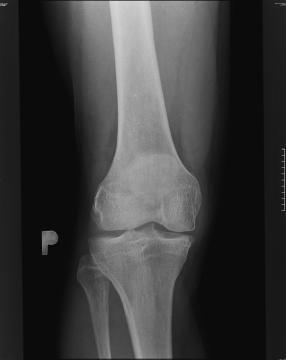

Pro větší náhled klikněte na obrázek

Dobrý den,je mi 54 let,mám bolesti kolen.Pravé koleno je horší,je nateklé i když v něm není voda,nemůžu nohu propnout.Momentálně chodím na alikace vlastní krevní plazmy a prozatím žádne velké zlepšení.Zajímá mě Váš názor na tuto léčbu a proč lékaři sami nenabizejí možnosti léčby,vše musím řešit z doslechu a vyprávění lidí s podobnými problémy.Stále mám dojem,že lékaři nemysli na pacienta,ale na peníze.Děkuji za odpověd.Topol